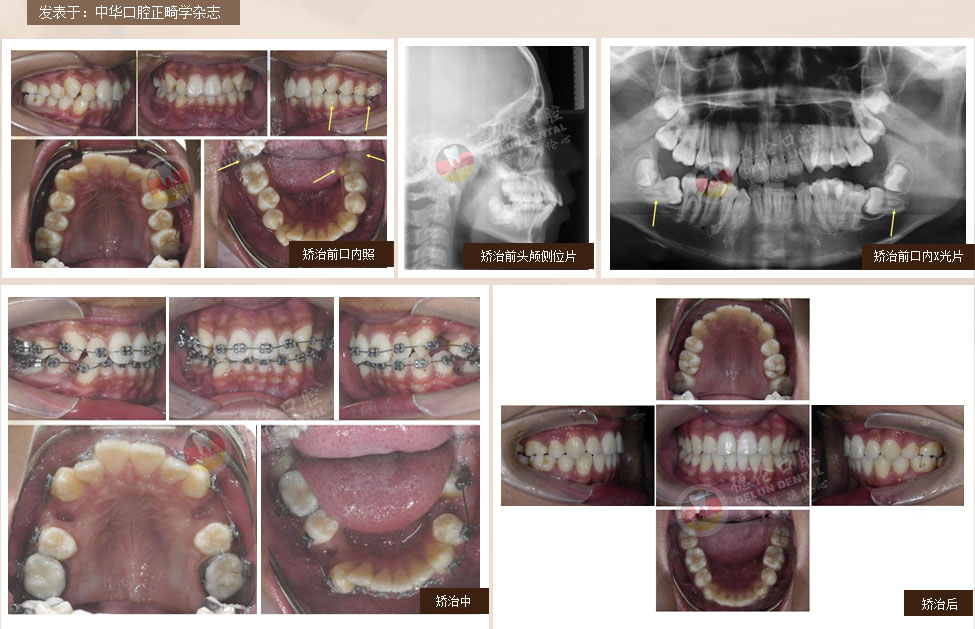

過去第一磨牙很早齲壞或缺失的患者只能拔除齲牙進行缺牙修復,若同時第三磨牙因阻生反復引起牙齒發炎疼痛,那么還要面臨拔除智齒恐懼??娫洪L通過多年臨床研究最終發明一種通過豎立智齒來代替齲壞或缺失的第一磨牙的方法,該技術刊登在2006全球權威口腔正畸學術雜志上,也稱為:“繆”院長的“妙技術”。

針對人群:下頜第一磨牙齲壞或缺失且下頜第三磨牙阻生。

備注:第一磨牙即六齡齒,人長出的第一顆恒牙。第三磨牙即智慧齒,最晚長出的恒牙。